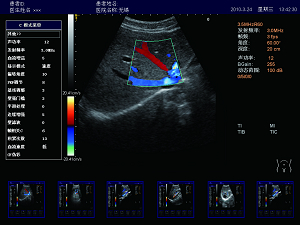

精確血流成像

智能識別血流運動和組織運動,使血流更充盈,組

織邊界更清晰。

實時三同步

B型、彩色和頻譜多普勒三種模式同時實時顯示,獲

得更精確地采樣定位,更直觀進行對比分析。

肝臟 脾臟 多普勒血流

高效的多譜勒技術

多普勒幀相關 血流圖像更平滑更清晰。

多普勒快速優(yōu)化 對于危重病人,兒童可以在短時間內(nèi)獲得最佳的血流成像。

壁濾波器 增強血流邊緣清晰度,產(chǎn)生精準的發(fā)射波形,達到最佳匹配效果,提高全聲場的回波質(zhì)量。